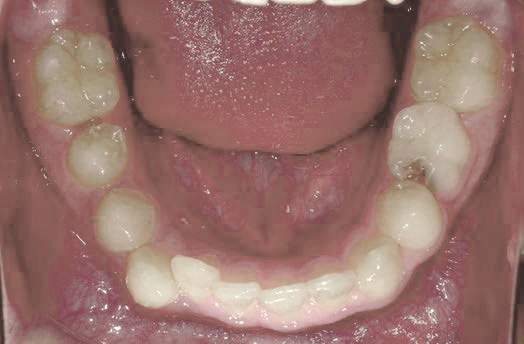

でこぼこでも大丈夫。抜かずに、あごから育てる矯正治療

Jさん (矯正開始時:8歳)

Before

After

歯がガタガタに並んでいて、前歯の真ん中の位置が少し左にずれていました。

奥歯が生えるためのスペースが足りず、永久歯が生えて来られない状況が確認できました。

また、飲み込むとき下くちびるに力が入ってしまうクセが見られ、お顔全体の成長が遅れている様子が確認できました。

治療を終えて

歯がきれいに生えるためのスペースをしっかり確保することができ、歯並びを乱していたお口のクセも改善されたため、奥歯が生えるスペースを確保することができました。

しっかり噛めるかみ合わせを作ることが、将来の健康につながるので「よく噛む」練習も続けてもらっています。

主訴・治療内容 歯がガタガタになってきたことに悩み、無料相談に来院されました。

治療期間 3年

費用 462,000円(税込)